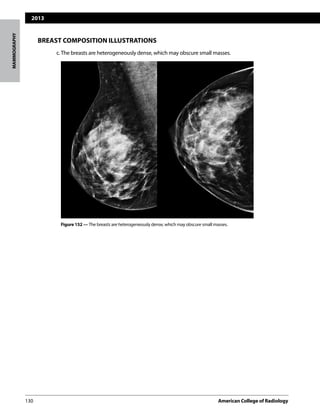

c.The breasts are heterogeneously dense, which may obscure small masses.

Figure 152 — The breasts are heterogeneously dense, which may obscure small masses.